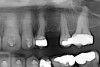

Fig 11. Corticotomy SFOT. A 42-year-old male presented with a history of extraction orthodontic therapy.

Figure 11

Fig 12 (and Fig 13). Incisors were too upright and had severe incisal wear. He was concerned about esthetics of the worn teeth and his insufficient lip support. Progress photo and panorex 9 months after corticotomies were performed on Nos. 6 through 11. Previous extraction sites were reopened orthodontically to improve function and fill lip support. Incisal edges were restored provisionally with composite resin. Note that despite the creation of adequate spaces to replace missing teeth, there is inadequate room for placement of dental implants because of severe tipping of all the anterior teeth. Osteotomy SFOT may have been a better choice because it would have allowed needed alveoloskeletal correction (without excessive tipping) instead of the primarily dentoalveolar correction common in corticotomy SFOT. Restorative dentist: Brad Jones, DDS.

Figure 12

Fig 13 (and Fig 12). Incisors were too upright and had severe incisal wear. He was concerned about esthetics of the worn teeth and his insufficient lip support. Progress photo and panorex 9 months after corticotomies were performed on Nos. 6 through 11.

Figure 13